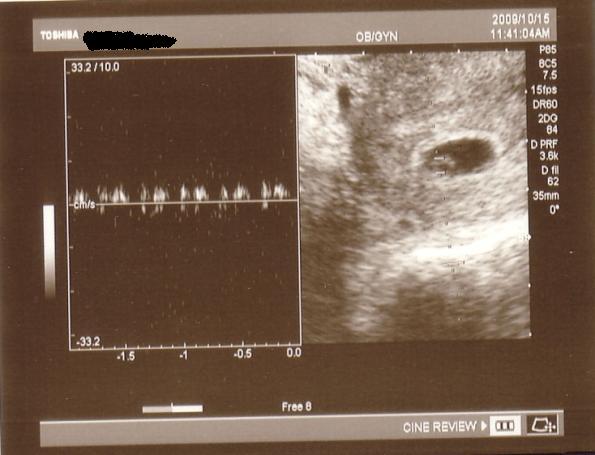

Minden rendben lurkóval, valóban fejvégű, 2100 gr. Kissé nagyobb lesz, mint Bátyja. Megint szóba jött a doki-dolog, hát eléggé meglepődött, amikor mondtam, hogy valószínűleg a dokim nézte el a gyerek fekvését (26. héten faros volt, utána éreztem egy fordulást -egyértelműen-, 30. héten mégis farosnak mondta a doki, azaóta nem éreztem fordulást és most viszont fejvégű (meg ugye előző héten is az volt) ergo szerintem a doki nézte el. No a lényeg, hogy megint beszéltünk erről, de mondtam Neki, hogy már nem akarok nagyon ugrálni... Amúgy a szülésznőmnek mondta, hogy majd együtt szülnek és hogy én leszek az... jééé emlékszik... És lenne mégegy téma ezzel kapcsolatban, de azt nem merem itt nyíltan...